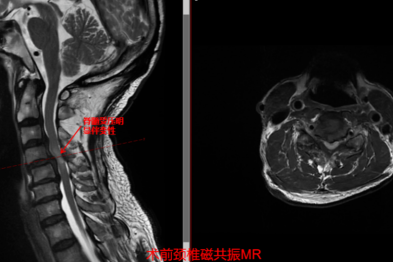

妙手解危局,仁术护安康 市中心医院脊柱外科助高龄危重颈椎病患者重获新生

2026-04-02 -